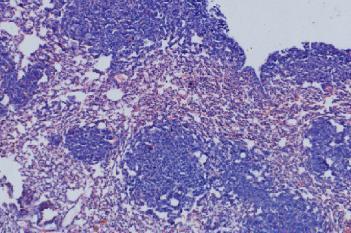

Figure 1

Tissue stained with H&E.